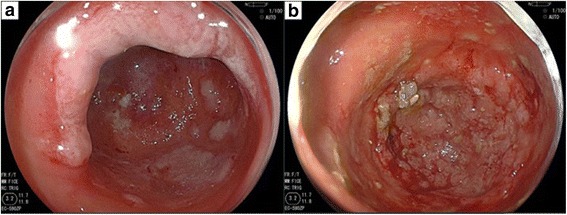

Early anal gland adenocarcinoma with a characteristic submucosal tumor-like appearance: a case report

この癌は、昔から「内視鏡で解らない癌」の代表として、教科書には必ず記載があります。表面が正常粘膜で被われており、腫れた痔核と区別がつかないのです。ある肛門の専門家は 「肛門腺癌の早期発見は偶然以外にはあり得ない」と述べており、肛門部皮膚癌の診断で外科手術を施行したが、実は肛門腺癌があることに手術後まで気付かなかったという報告や 「75ミリの癌が解らなかった」という報告もあります。

下記の報告は、世界的に極めて珍しい「初期の肛門腺癌」の報告なのですが、「浅い層の肛門腺」に癌が発生したもので、偶然の幸運により発見された病変です。